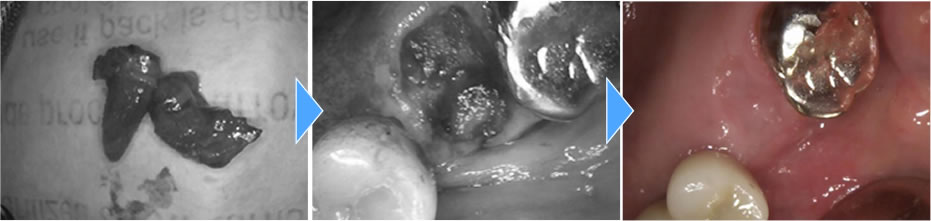

今回は上顎洞までの骨の厚みが足りなかった為に上顎洞粘膜を挙上し、骨を作ると同時にインプラント体を埋入していきました。粘膜を挙上する方法としては水の圧力を利用して行っていきました。

上部構造の装着・治療完了

そこから5ヵ月おき、骨の吸収が無く、骨とインプラント体がオステオインテグレーションしている事を確認し、上部に歯を作成していきました。

結果、横の歯の歯茎が下がりインプラント体が見える事なくしっかりとした歯を作成する事ができました。